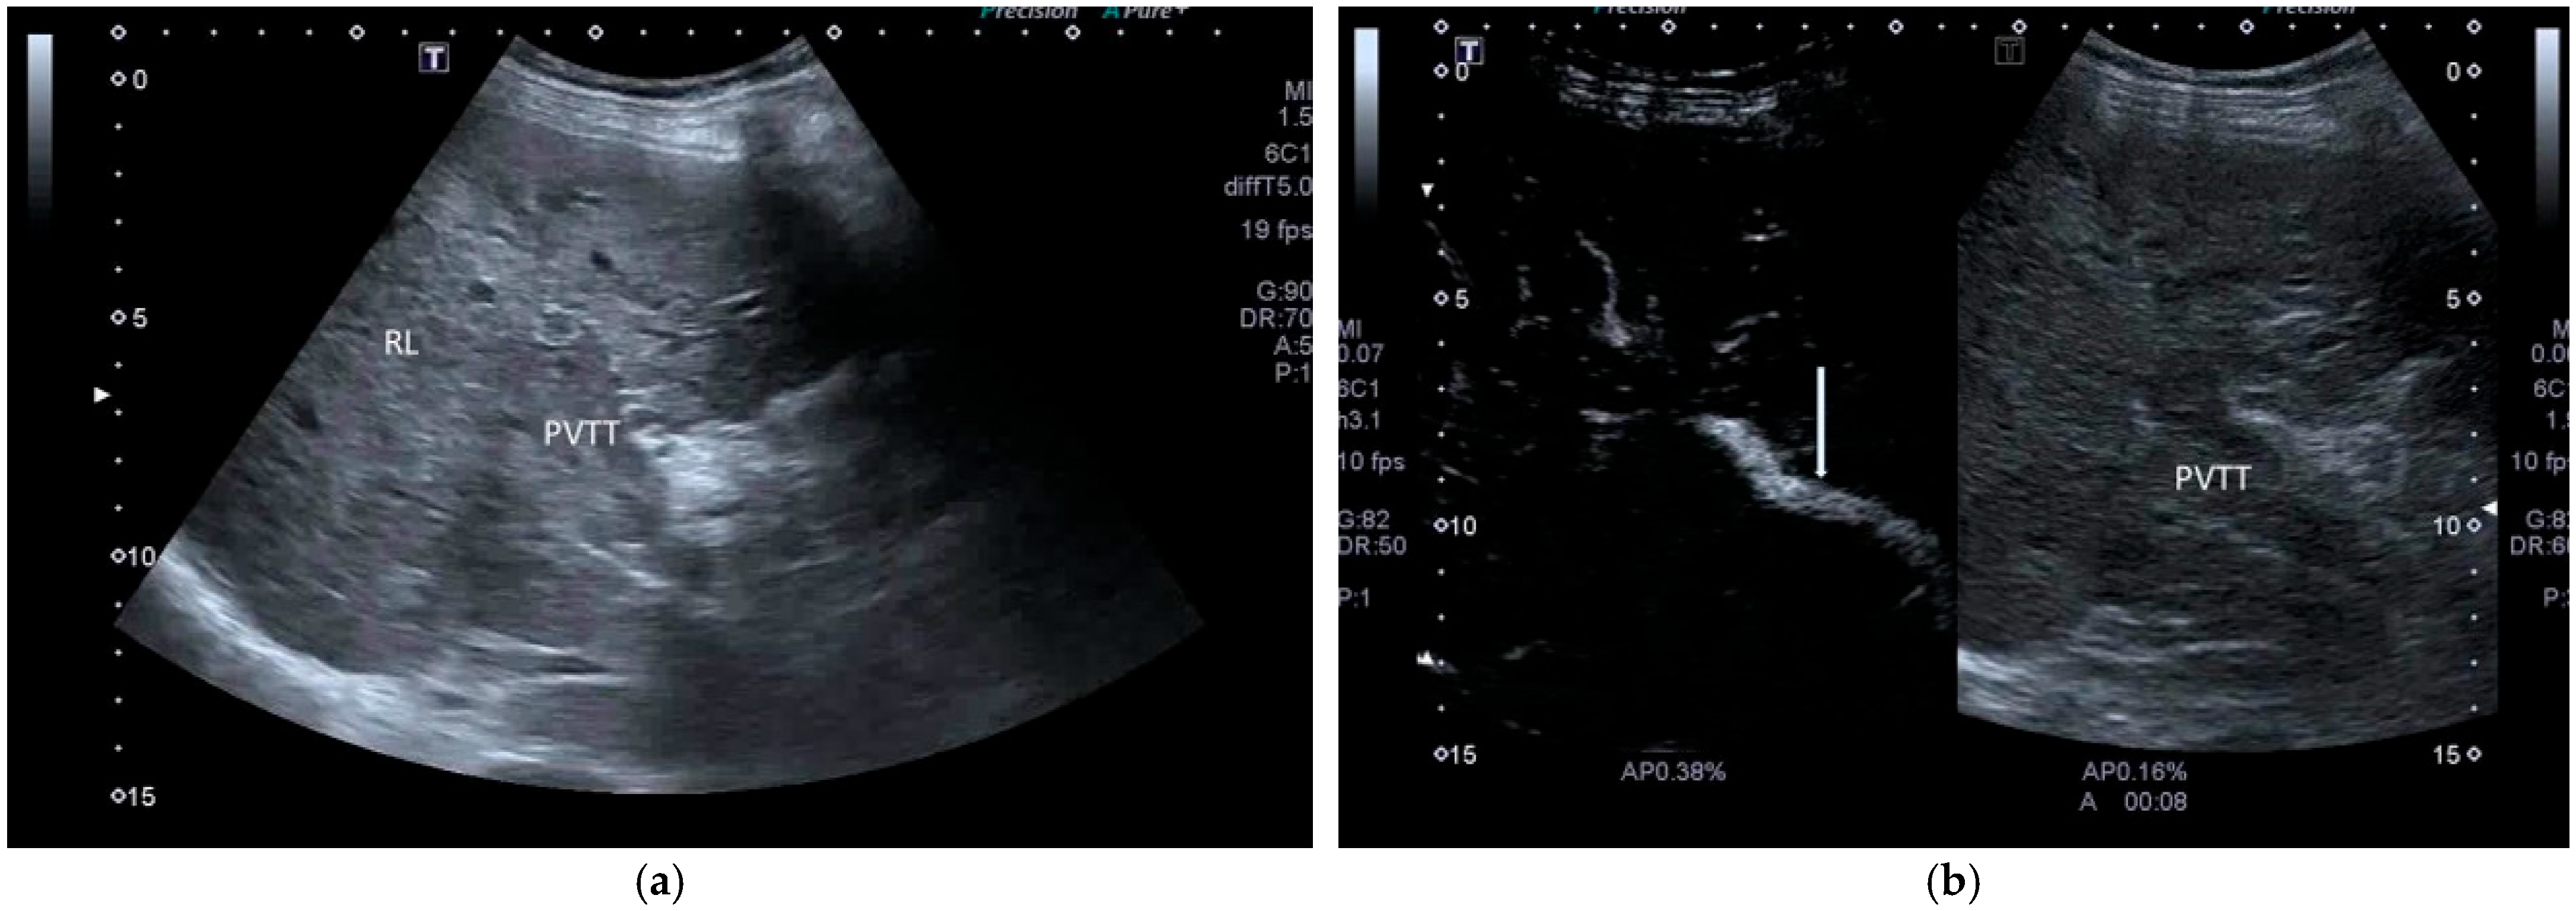

- Cerrito, L.; Ainora, M.E.; Di Francesco, S.; Galasso, L.; Gasbarrini, A.; Zocco, M.A. The Role of Contrast-Enhanced Ultrasound (CEUS) in the Detection of Neoplastic Portal Vein Thrombosis in Patients with Hepatocellular Carcinoma. Tomography 2023, 9, 1976–1986. [Google Scholar] [CrossRef] [PubMed]

| CEUS LR-TIV (tumor in vein) |

|